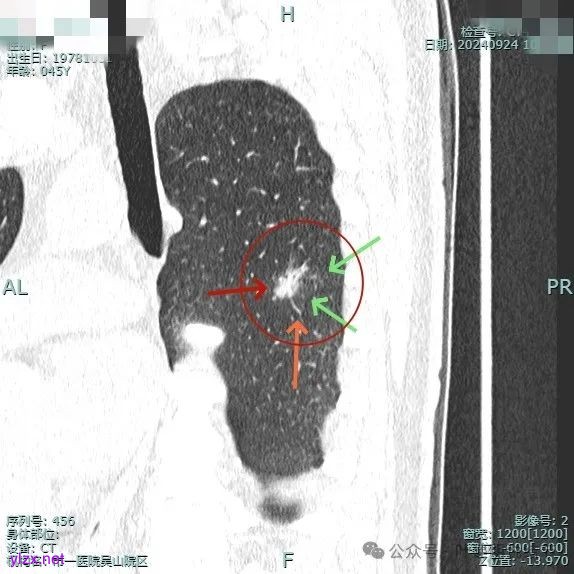

时间很快到了2025年3月,结友又来我门诊复查,我还以为她在别处开了刀了呢,结果并没有,说是与家人商量后决定吃中药三个月看看能不能好。我们来看看再复查的情况,中药有没有起作用:

总体感觉三处病灶边缘的淡磨玻璃成分好转不太明显了,实性成分较前略显致密点,大小与形态是说不上显著变化的。所以有几点可以肯定:1、消炎没有效;2、中药没有用;3、考虑多原发肺癌,且为浸润性腺癌可能性大些,得手术!